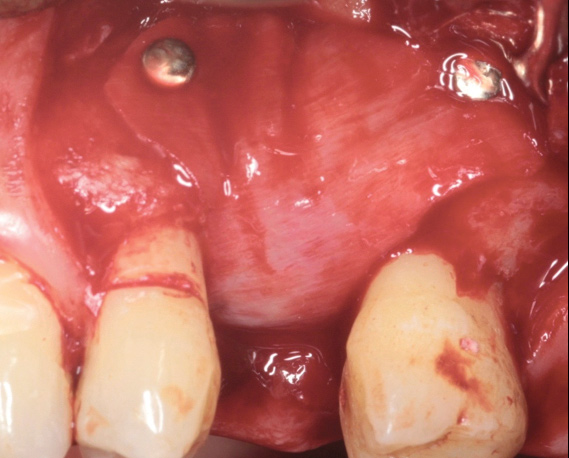

The first step in preventive strategies must be to perform a correct diagnosis of the peri-implant condition by accurately assessing the health of the peri-implant hard and soft tissues through periodontal probing and periapical radiographs at the time of definitive prosthetic installation. These measurements should be considered the baseline diagnosis and, therefore, represent a true starting point for evaluating the changes on the radiographic bone levels and probing pocket depths (PPD) at future recall appointments (Figure 1 and Figure 2).6 Although probing depth measurements of peri-implant tissues do not have the same diagnostic value as probing periodontal tissues, there is evidence that BOP is the most objective sign of peri-implant tissue inflammation; significant deepening of PPD compared with baseline measurements is also a sign of disease that indicates the need to perform a radiographic evaluation (Figure 3 through Figure 5).6,10,11

Fig 1. Baseline measurements at the time of prosthetic delivery: probing pocket depth and

Figure 1

Fig 2. periapical radiographs.

Figure 2